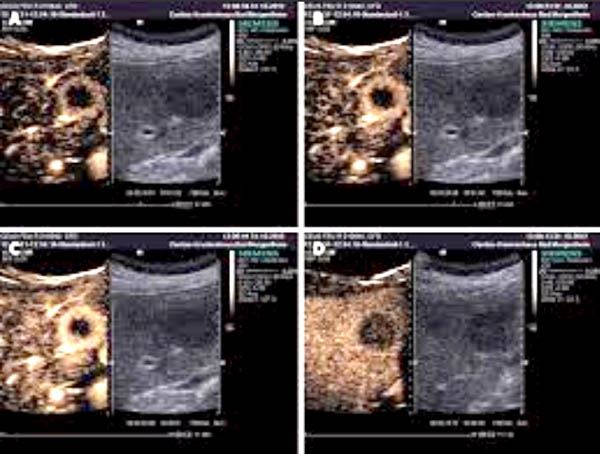

Hình 1

Đầu tiên, bệnh nhân được đưa vào một bệnh viện, sau đó siêu âm bụng và chụp cắt lớp vi tính ổ bụng (CT-scanner) được thực hiện. Siêu âm cho thấy một khối thương tổn [38 × 29 mm]. Các hình ảnh CT-scanner xác nhận phát sự hiện diện của khối này bằng cách tìm ra được một khối [3 × 4 cm] giảm dần đậm độ về trung tâm, tổn thương ở thùy trái của gan. Ngoài ra, ở vùng rốn gan, có hạch bạch huyết 31 mm đã được xác định.

Các nghiên cứu hình ảnh được lặp lại sau đó nhiều lần sau khi hội chẩn của cả nhóm. Những hình ảnh CT-scanner trước khi điều trị ban đầu cho thấy có khối rắn nhạt màu dần dần về trung tâm [7 × 5,5 cm] trong các phân thùy gan 2, 3 và 4. Các khối u cũng được tìm thấy, gây ra tắc mật ở thùy trái. Hơn nữa, hạch đã được xác định, với các hạch bạch huyết lớn nhất là 2,7 cm, đường kính trong khu vực khoang tĩnh mạch portacaval.

Bệnh nhân sau đó được ra viện và yêu cầu tái khám 3 tháng sau để theo dõi diễn tiến. Kết quả của một CT-scanner khác sau đó cho thấy sự phục hồi cả khối u và các hạch lympho rõ ràng trên hình A và B.

Hình (A): Chụp CT-scanner ổ bụng kiểm tra cho thấy một khối thương tổn giảm âm, giảm dần độ đậm về trung tâm 7 × 5,5 cm trong nhu mô gan.

Hình (B): Một hình ảnh CT scanner khác cho thấy sự phục hội và xóa mờ các “khối u” ở trong nhu mô gan.